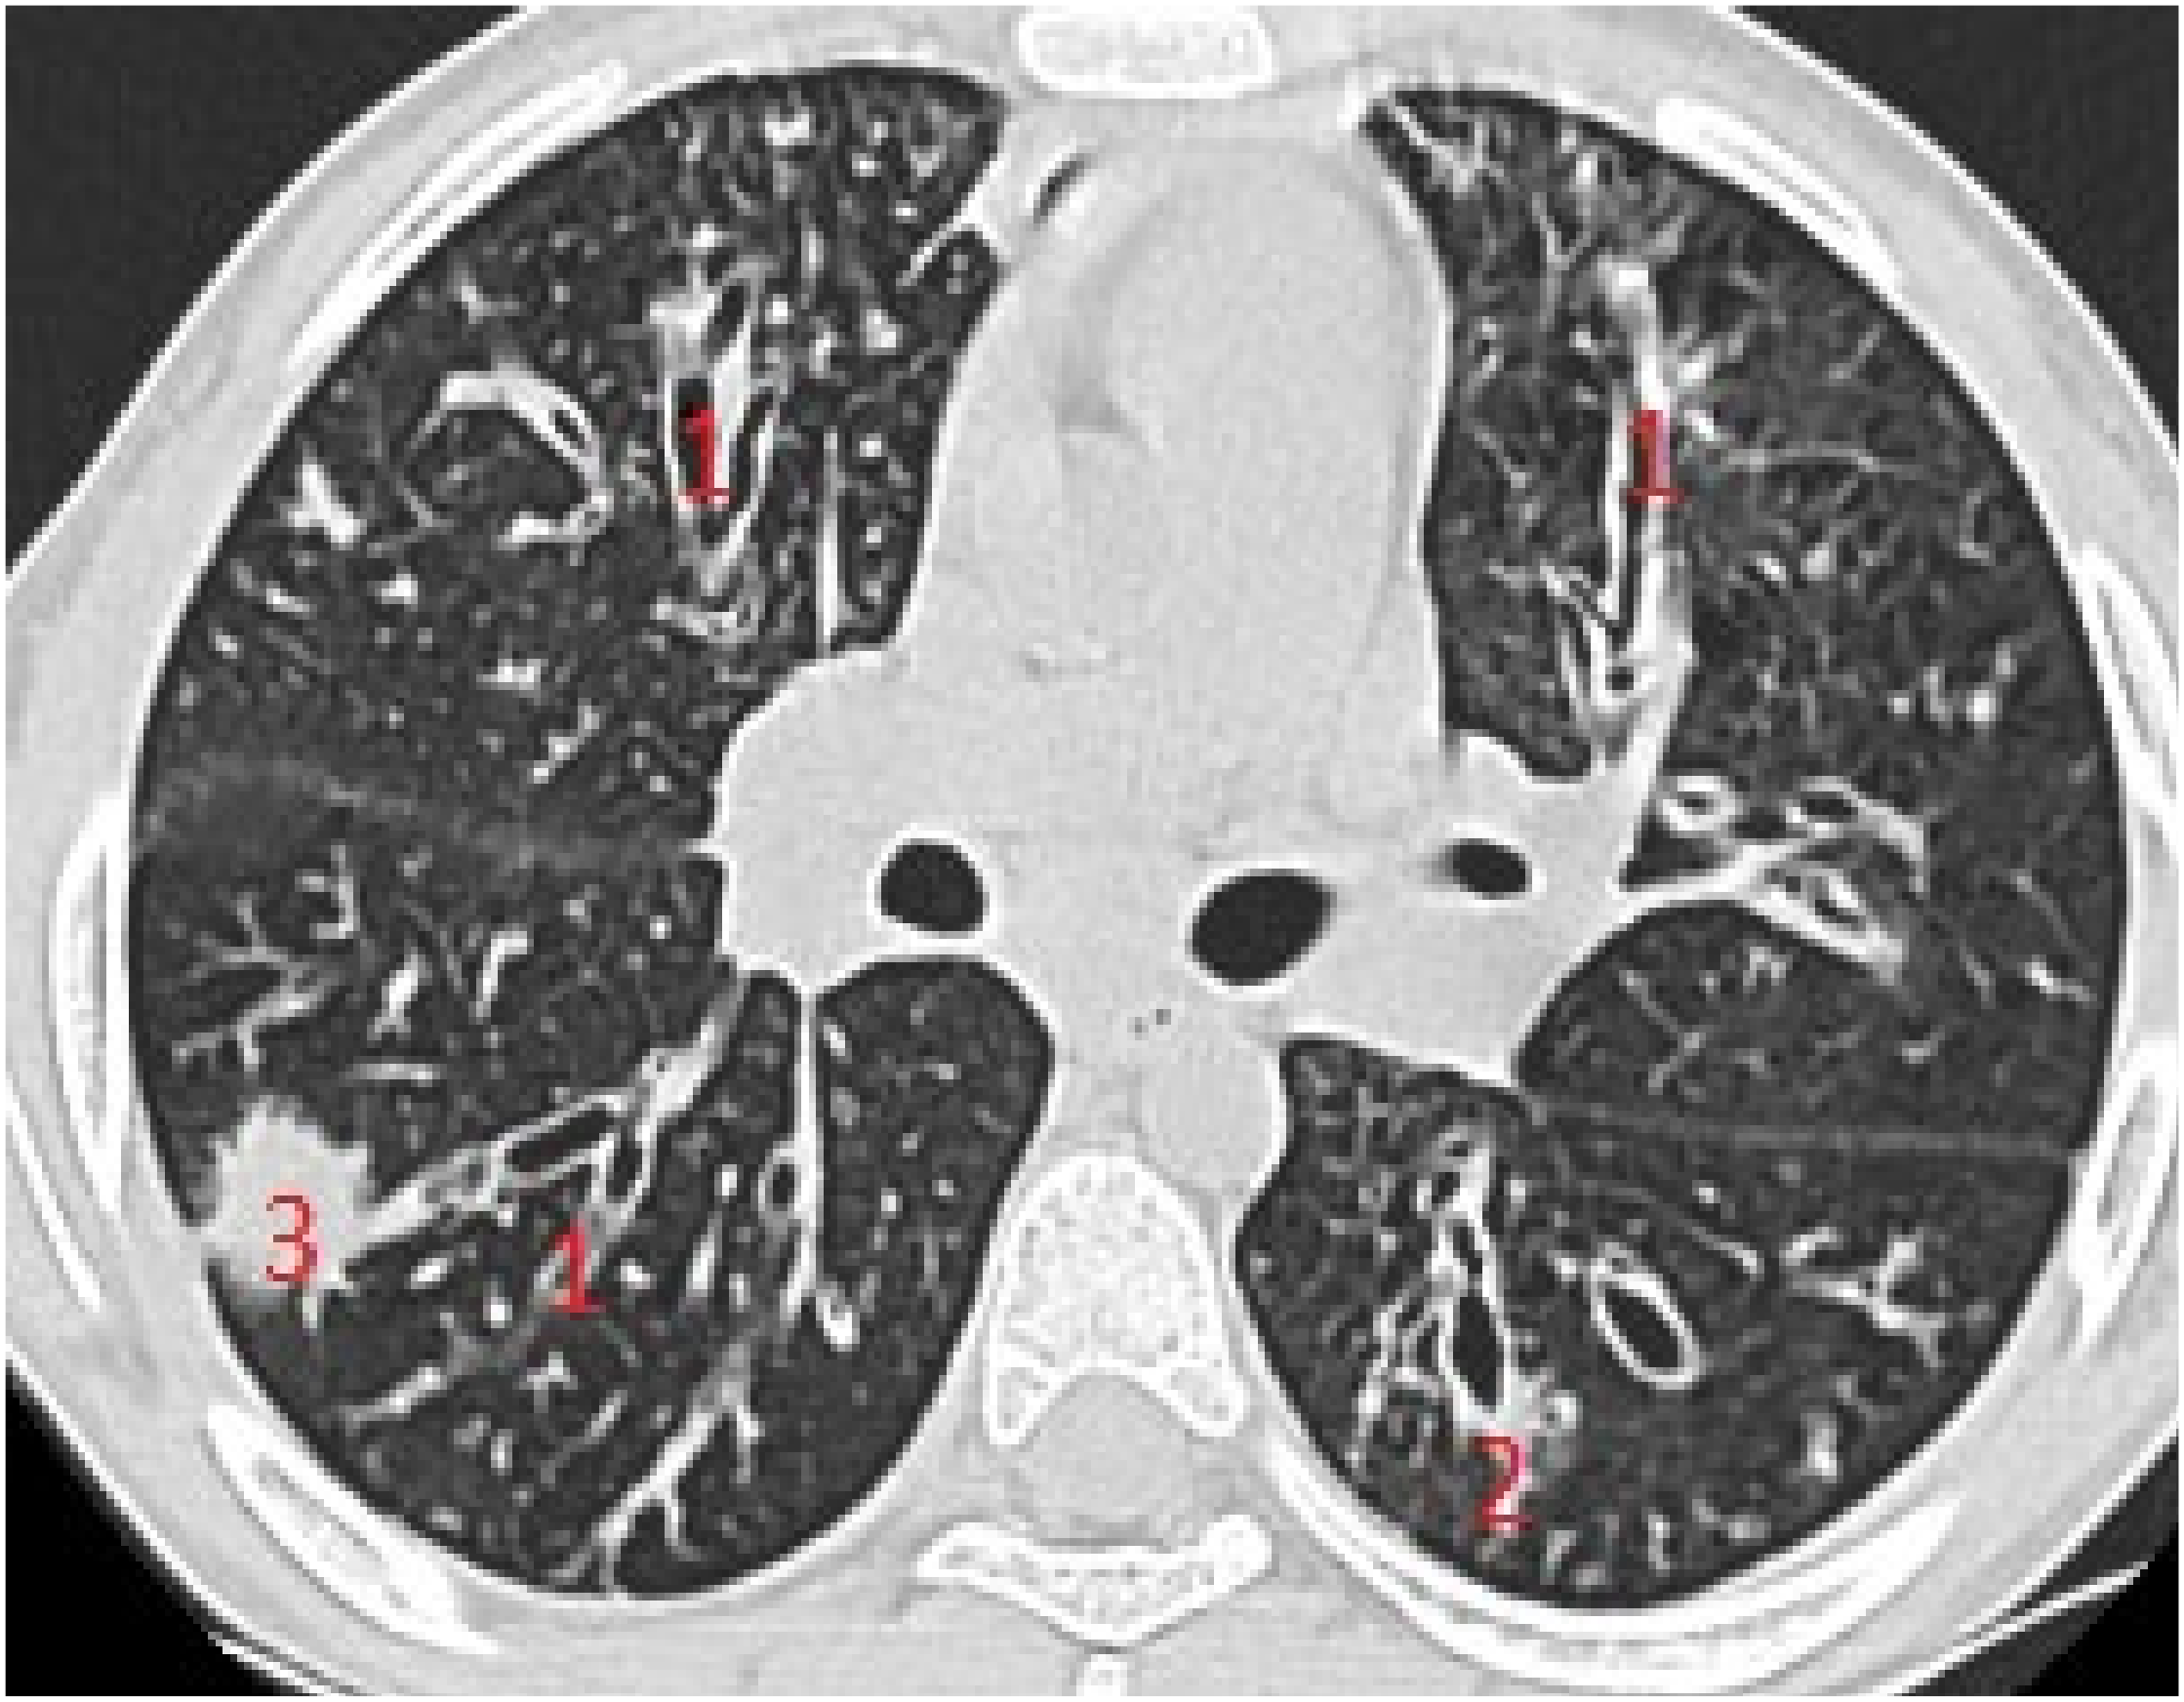

In patients with important structural lung damage (Figure 7), quantified as severe disease, expressed by a CT score > 66, the correlation was strong (rs = 0.83), with statistical significance (p = 0.002).

The assessment of LUS sensitivity and specificity in bronchiectasis detection varied with the form of bronchiectasis: for cylindrical bronchiectasis(Figure 8A,B), LUS Se = 77.7%, Sp = 9%, PPV = 80.7%, and NPV = 76.9%, while for saccular bronchiectasis (Figure 7), a moderate Se = 68.4%, with good Sp = 94.9%, PPV = 88.8%, and NPV = 94.7% were found.

Figure 7. (A) LUS: coalescent B lines, erased A profile, loss of aeration, left hemithorax. (B) LUS image with subpleural consolidations, coalescent B lines, and left hemithorax. (C) CT scan of the same patients: (1) varicose bronchiectasis with middle 1/3 of lung extended and moderate bronchial wall thickening; (2) saccular bronchiectasis with mild and moderate wall thickening; and (3) zones with increased attenuation of pulmonary parenchyma (alveolar infiltrates).